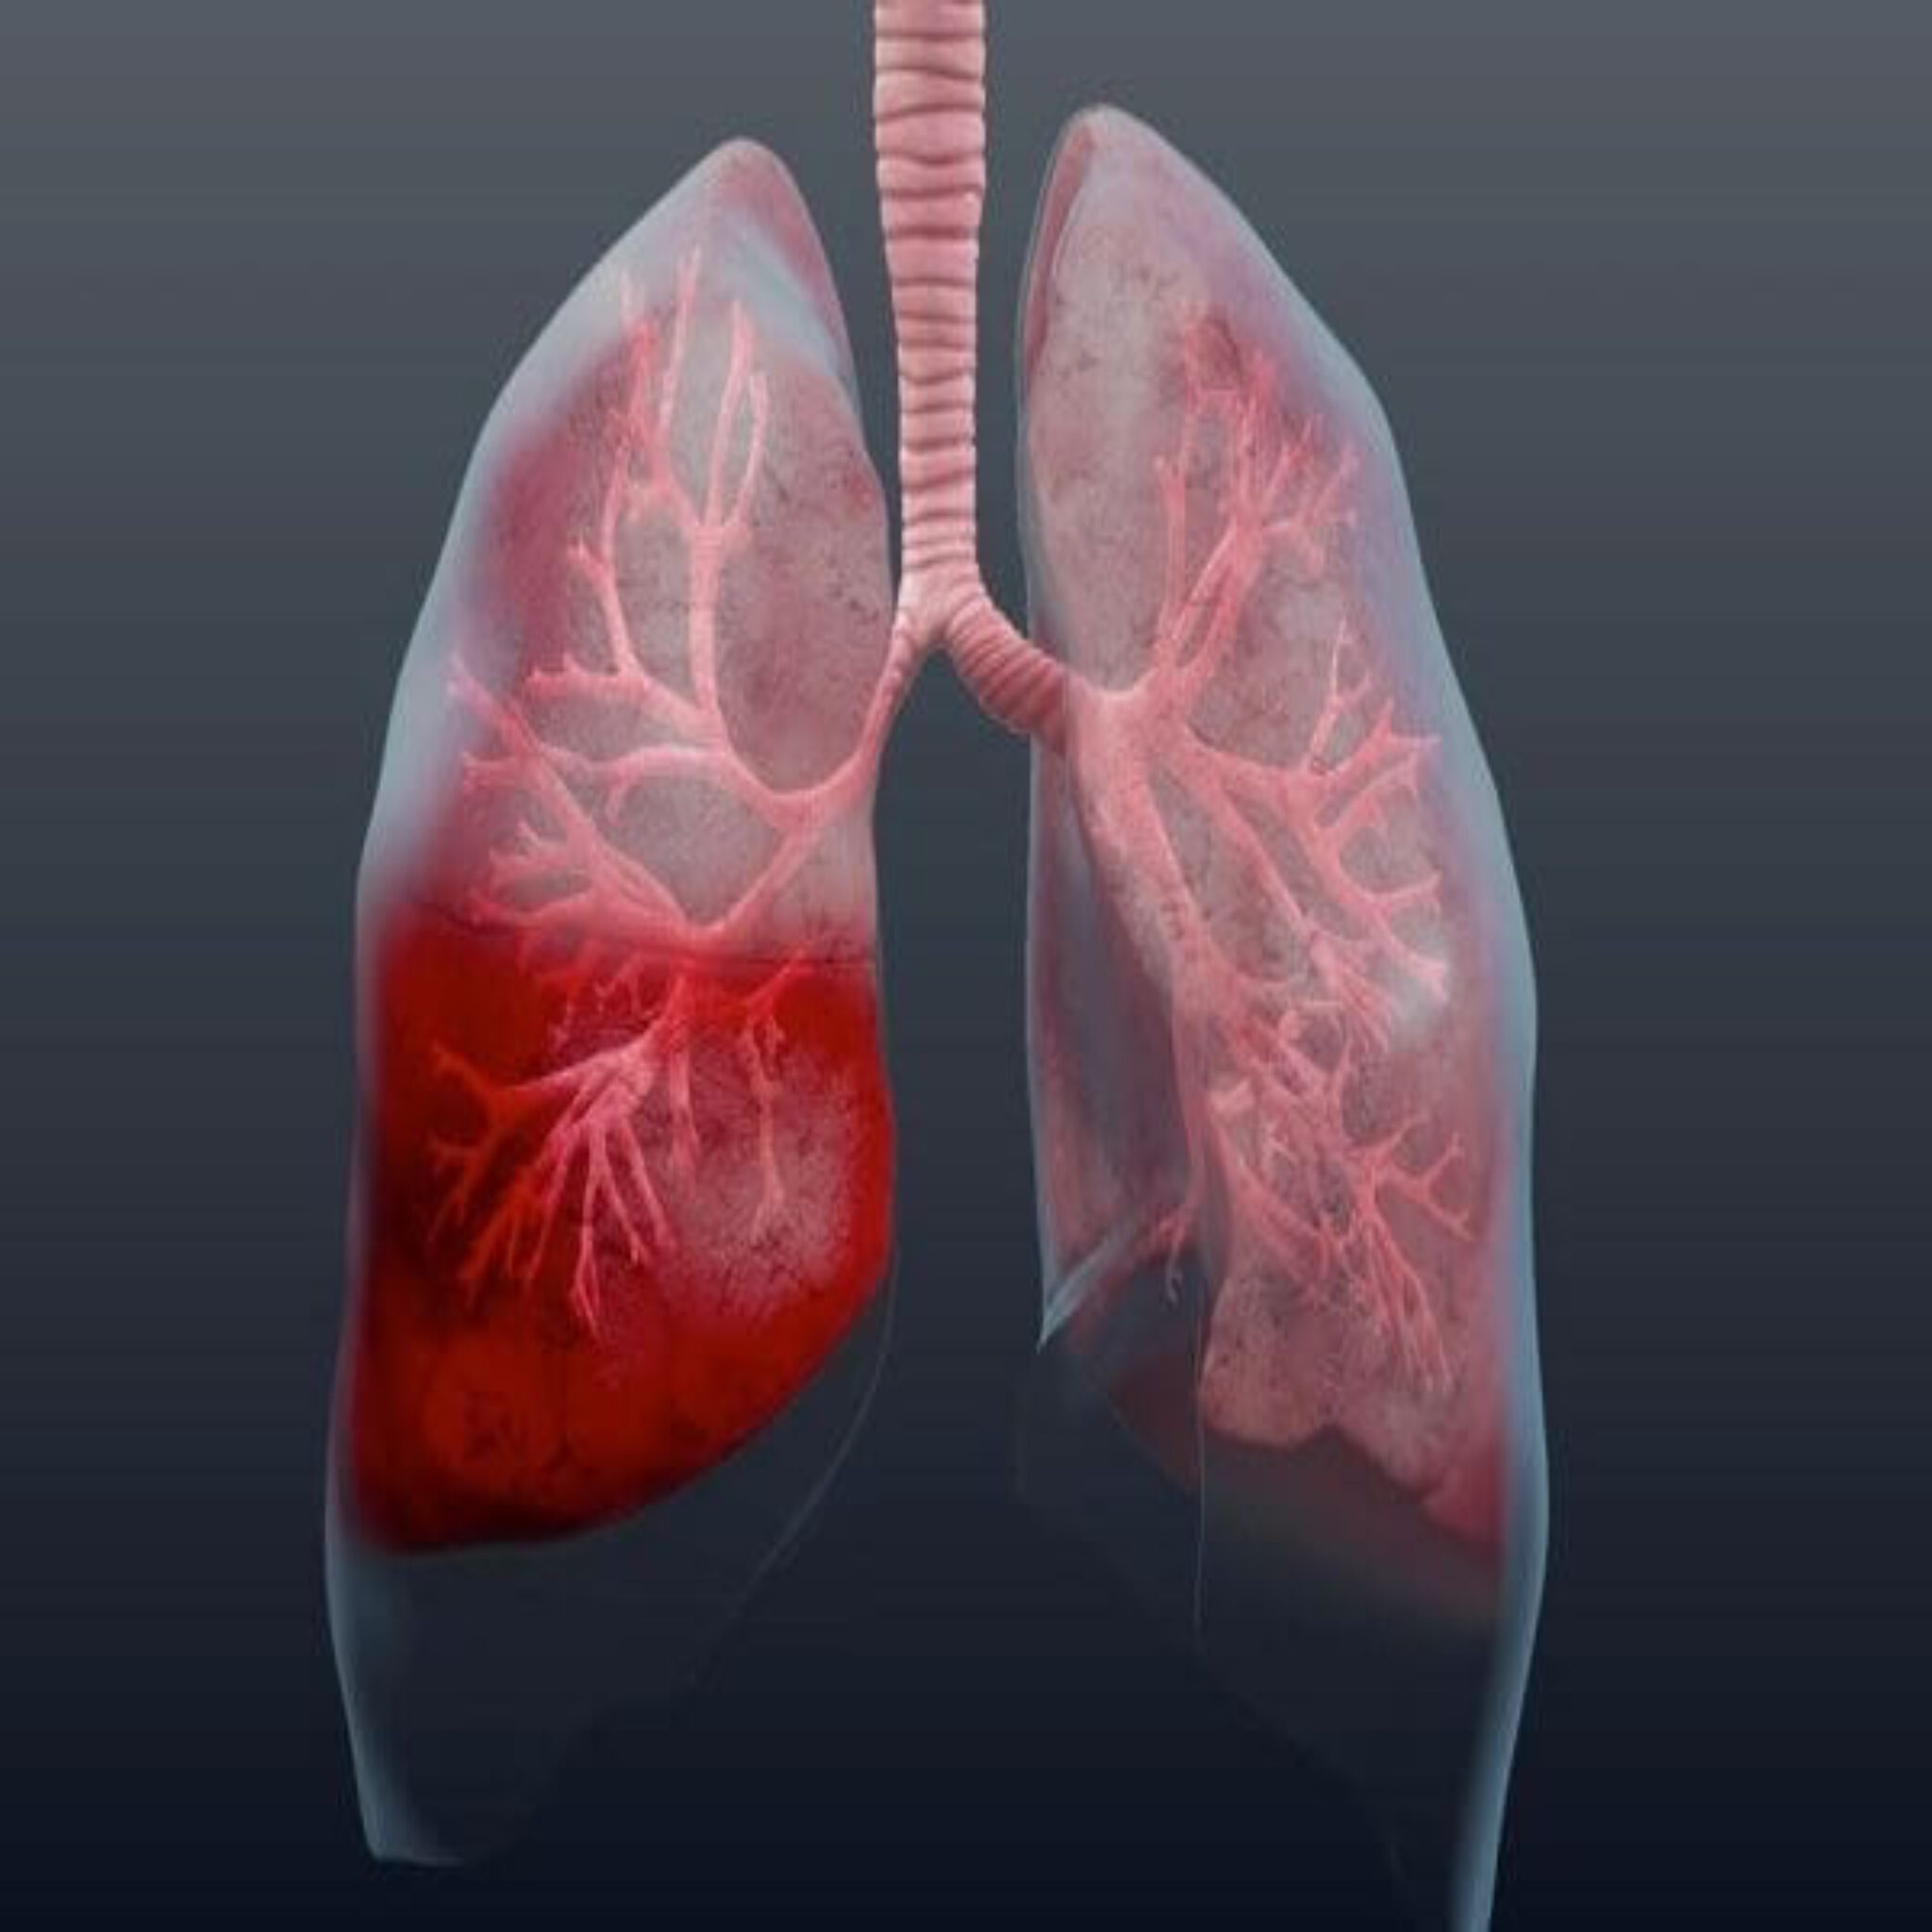

Пневмония - это серьезное заболевание легких, которое может быть вызвано различными причинами, включая бактериальные, вирусные и грибковые инфекции. Для того чтобы наглядно показать симптомы, диагностику и лечение этого заболевания, картинки могут быть очень полезны.

Картинки с симптомами пневмонии

В этом разделе представлены изображения, демонстрирующие различные симптомы пневмонии, такие как кашель, одышка, боль в груди и повышенная температура. Эти картинки могут быть использованы для обучения и презентаций в области медицины и здравоохранения.